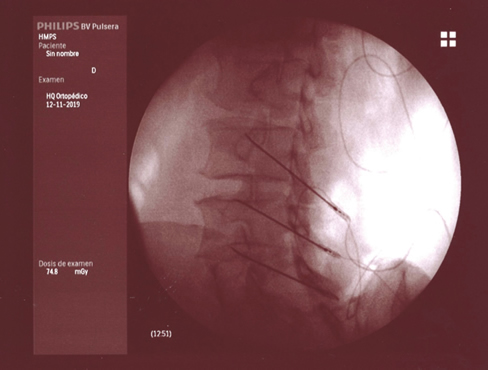

Aunque la articulación de la cadera se afecta con menos frecuencia que la rodilla, también parece despertar menos curiosidad e interés de las publicaciones, pues son muchas menos que sobre la rodilla. La inervación de la cadera está bien estudiada (24,25,26). El resumen de todas estas publicaciones es que la cápsula articular de la cadera recibe inervación en su cara anterior de los nervios femoral (cuadrante supero externo) y obturador en el cuadrante ínfero interno. Se ha demostrado que la denervación de la cápsula articular en la cara anterior produce un alivio del dolor en los pacientes con coxartrosis avanzada que no pueden ser tratados con una prótesis total debido a diferentes factores (edad avanzada, comorbilidades o riesgo quirúrgico elevado). Esquematizando mucho la inervación de la cara anterior de la cadera resumiría en que las ramas articulares del femoral se localizan en la parte superior y externa del cotilo femoral, mientras que las ramas articulares del obturador se localizan en la parte inferior sobre la rama descendente del isquión en su unión con el borde inferior del cotilo. La primera publicación describiendo una técnica de denervación con radiofrecuencia de la cara anterior de la cápsula articular de la cadera se produce en 2001 (27), en el que Kawaguchi describió una técnica con una aguja colocada en el borde anterolateral del cotilo para lesionar las ramas del nervio femoral, y otra en la parte inferior en la unión entre la parte externa de la rama pubiana y la descendente del isquión para lesionar las ramas del obturador mediante radiofrecuencia térmica; obtiene buenos resultados en disminuir el dolor en pacientes con coxartrosis. En los años siguientes se siguen publicando trabajos con un abordaje similar al de Kawaguchi, con control radiológico o con control ecográfico (28,29,30), así como algunas series de casos con radiofrecuencia pulsada (31). En 2018 se publicó una revisión de la evidencia que concluye que ninguno de los trabajos publicados es un RCT y que es necesaria su realización con una metodología de alta calidad para poder valorar el papel de estas técnicas. En 2008 (32)una publicación hace una valoración de la anatomía radiológica del nervio obturador, analizando la dificultad que tiene lesionar todas las posibles variaciones anatómicas de las ramas articulares del obturador con una sola aguja, además de analizar la dificultad que presenta el abordaje anterior de estas ramas debido a la presencia del paquete vásculo-nervioso femoral, que se interpone en el trayecto de las agujas, recomendando introducirlas de manera anterolateral con un ángulo de al menos 70° con el plano vertical. Termina proponiendo la realización de tres lesiones para asegurar la neurotomía de la mayoría de las ramas articulares. Basándonos en este artículo, desarrollamos una variación de la técnica de Kawaguchi en la que utilizamos tres agujas en la zona superoexterna del cotilo, y otras tres agujas en la parte inferior en la rama ascendente del isquión, introducidas de manera lateral con un ángulo al menos de 70° respecto al plano vertical, y realizando una lesión en empalizada con radiofrecuencia térmica bipolar entre cada dos agujas (Figura 3), obteniendo buenos resultados en más del 60 % de los pacientes tratados, que fue objeto de una comunicación a un congreso de la SED. Estas técnicas tienen que ser validadas en cuanto a su reproducibilidad y resultados, careciendo en estos momentos de evidencia, y de la estandarización de las referencias anatómicas y radiológicas para su realización (33).

Fig. 3.

La neurotomía por radiofrecuencia de las ramas articulares de los nervios femoral y obturador es una técnica no estandarizada, cuyas referencias anatómicas y radiológicas están todavía sin establecer y que precisarán de la realización de RCT de calidad para poder conseguir datos de evidencia sobre su utilidad. En mi opinión la realización de lesiones en empalizada con dos o tres agujas puede mejorar la posibilidad de lesionar la mayoría de las ramas sensoriales que, debido a las variaciones anatómicas, pueden ser difíciles de lesionar con una sola aguja. El principal peligro y complicación de esta técnica es la aparición de hematomas por punción accidental de la arteria femoral, si el abordaje se hace de manera vertical. La técnica se puede realizar con control radiológico o ecográfico, ofreciendo la ecografía la ventaja de poder visualizar el paquete vasculonervioso femoral.